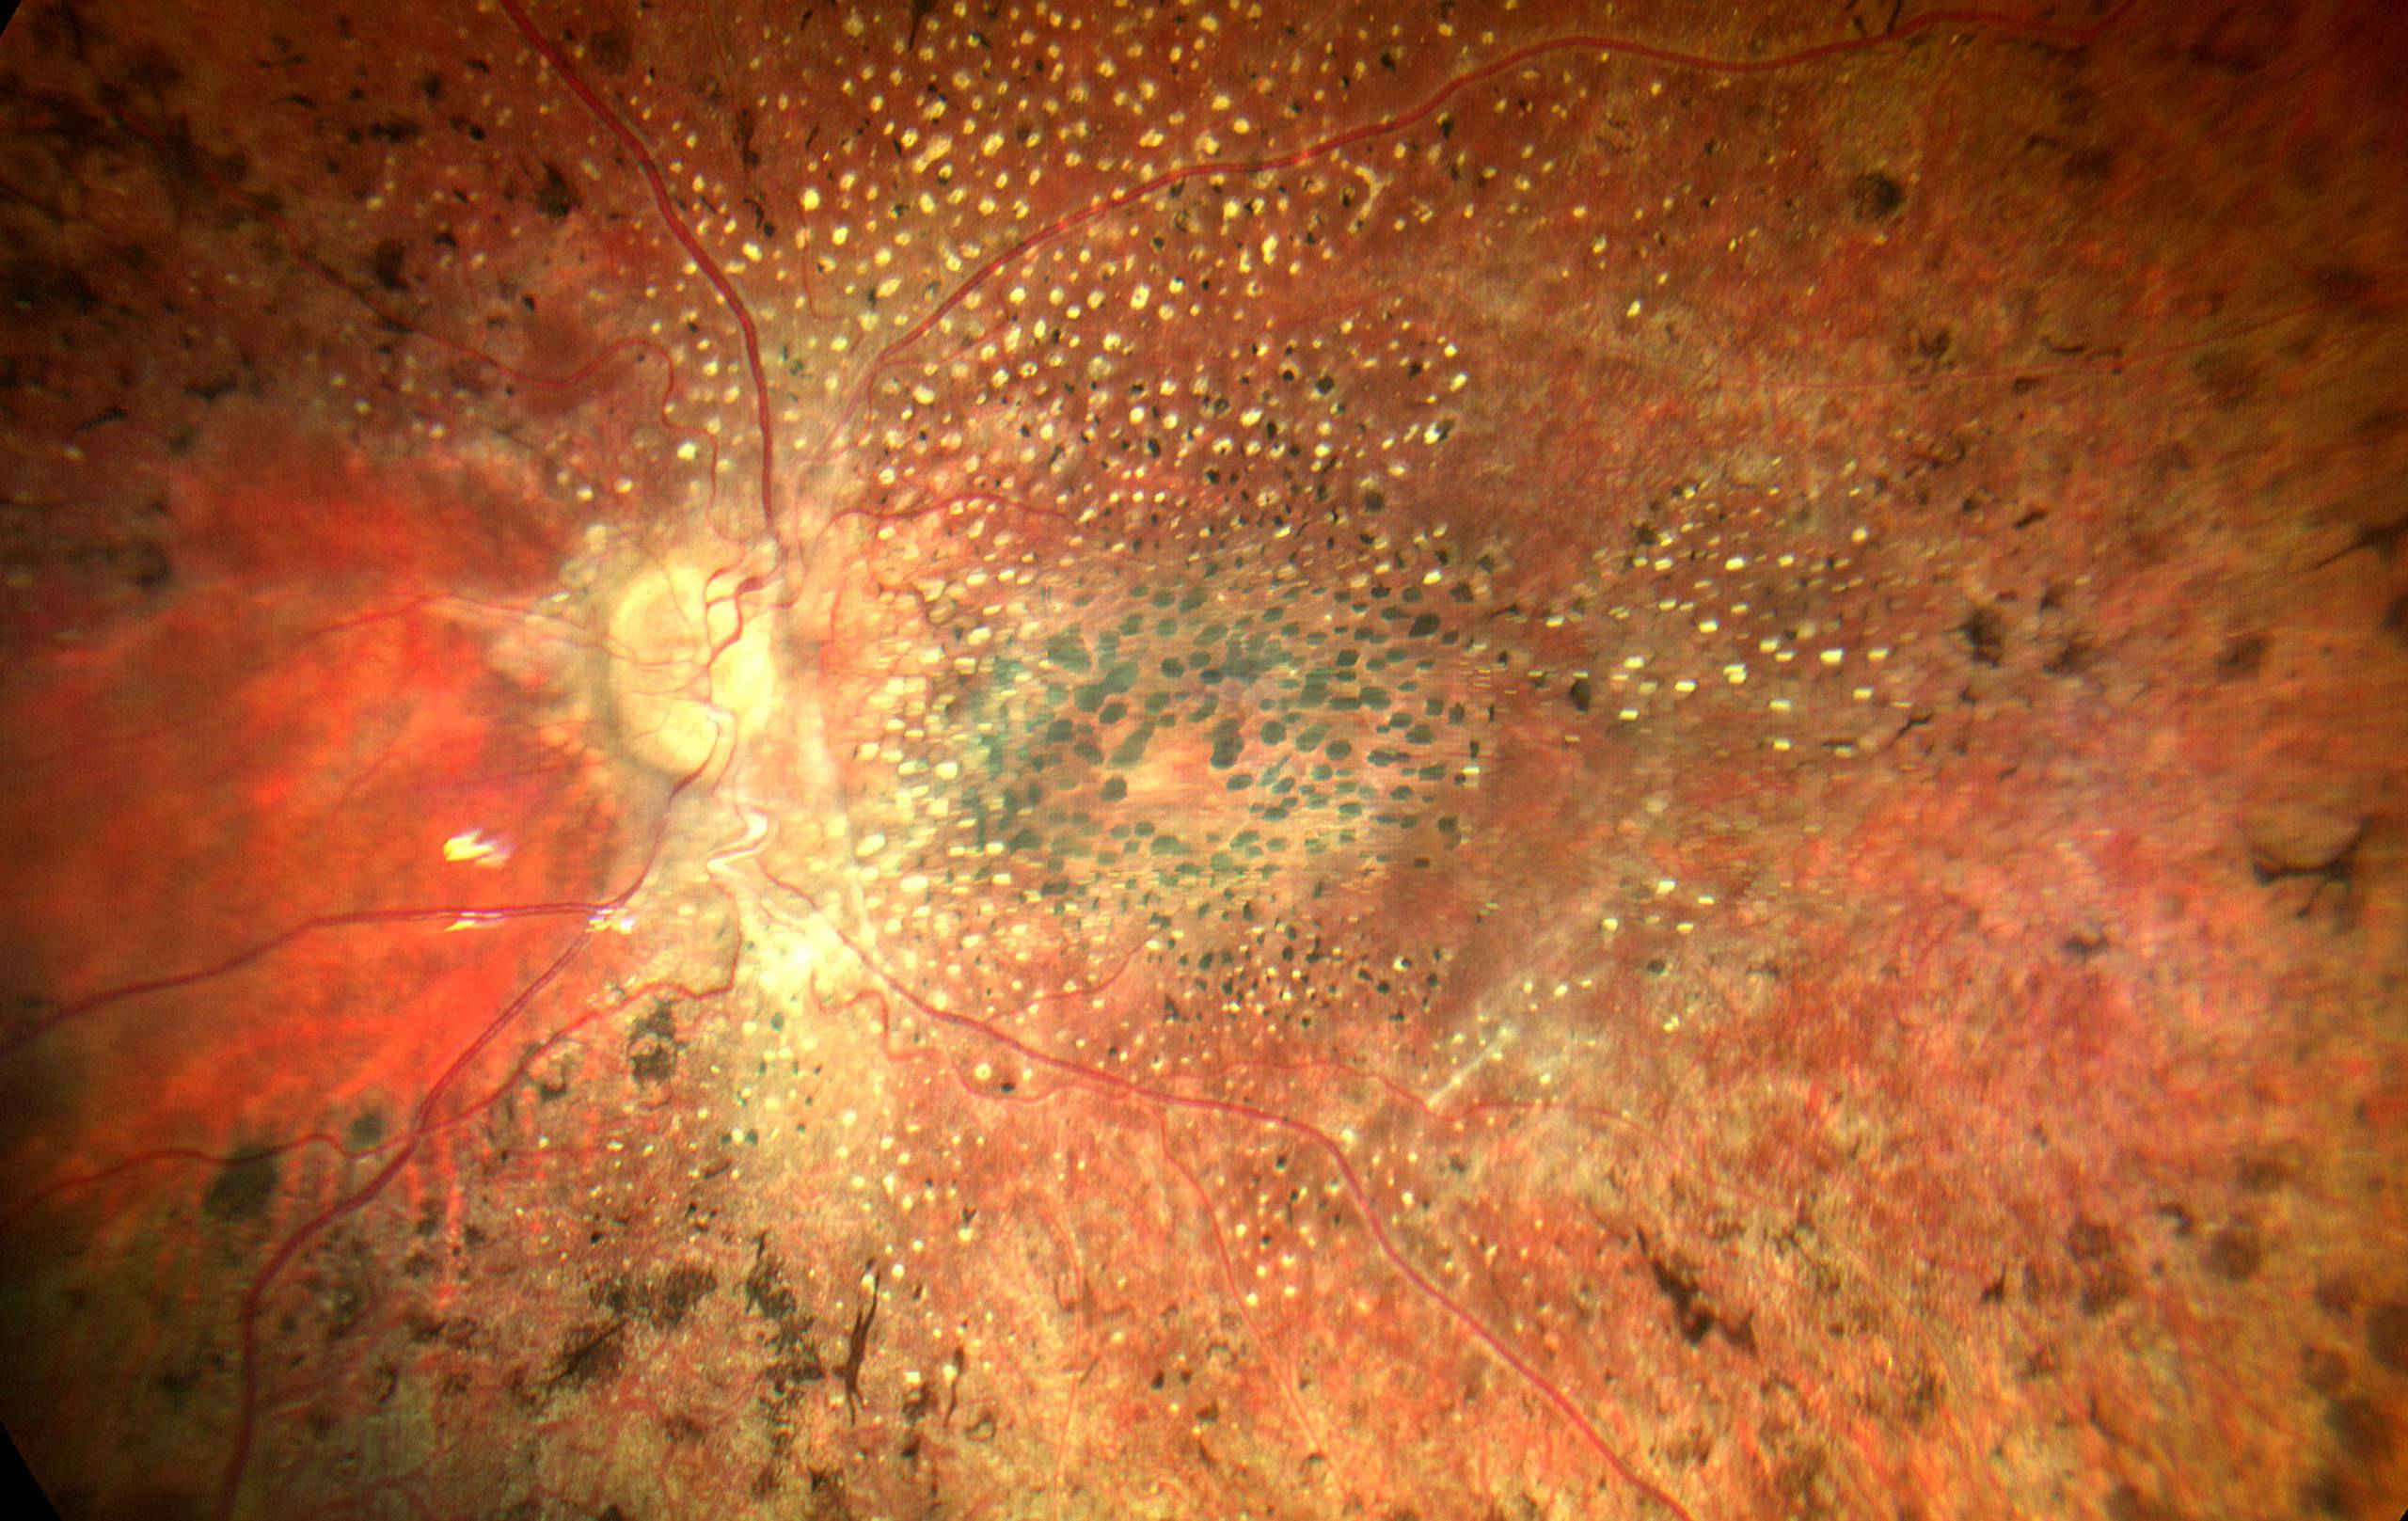

La Amaurosis Congénita de Leber es una enfermedad ocular hereditaria que afecta principalmente a la retina, la capa más interna…